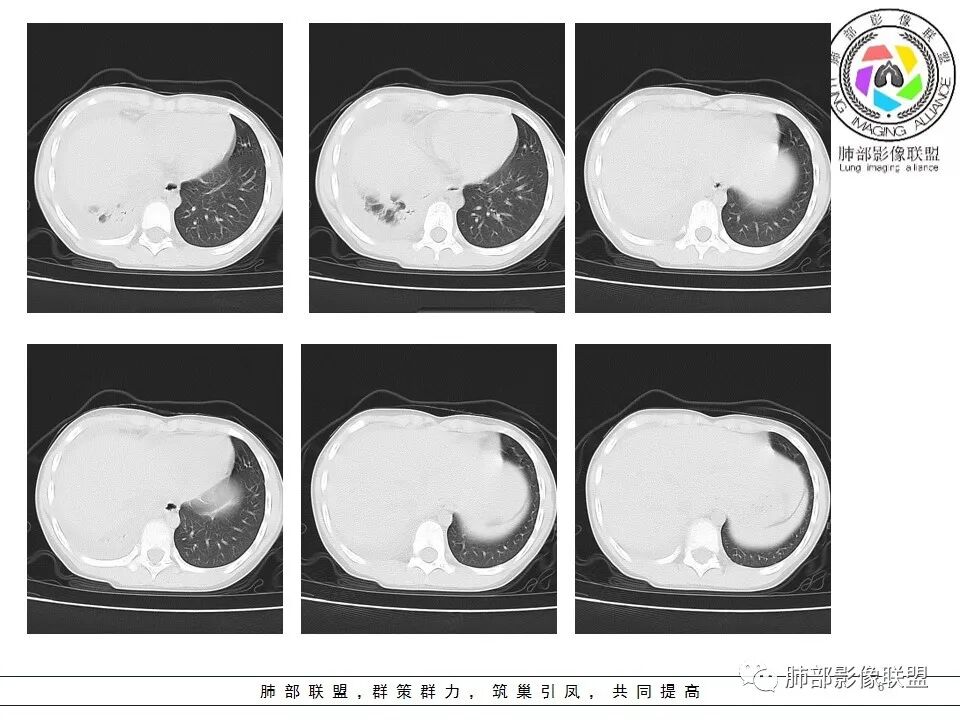

一切∮随缘: 前纵隔偏右侧实性占位,向右肺挤压,右肺膨胀不全,右侧胸水,心包似乎也有胸水,病灶较大无增强,平扫密度欠均匀,内部似可见低密度坏死及高密度钙化影,年轻男性,考虑恶性,生殖细胞肿瘤(精原细胞瘤?恶性畸胎瘤?),鉴别神经母细胞瘤,肺母细胞瘤,PNET?

秦化君: 右前上纵隔软组织密度肿块,边缘部分清晰澎隆,与血管及心包间界线不清,密度较均匀。挤压相邻肺组织形成膨胀不良,侵及胸膜形成胸腔积液。双肺内见随机分布结节。考虑纵隔恶性占位(肺及胸膜转移),生殖细胞瘤,畸胎瘤,淋巴瘤。建议穿刺活检。

放射线 (王秀仙): 右侧前纵膈巨大肿块,与纵膈大血管分界不清并受压,右肺组织受压膨胀不全,密度不均,内可见高密度钙化及低密度坏死区,双肺多发结节状转移灶,右侧胸腔积液,年轻男性,考虑生殖细胞肿瘤,精原细胞瘤可能性大。

宇宙: 男性小孩,右前纵膈不规则肿块,与心脏及大血管分界不清,邻近肺组织受压,其内可见钙化及低密度坏死,两肺多发类圆形结节,右侧胸水,考虑精原细胞瘤伴两肺及胸膜转移,鉴别恶性畸胎瘤。

金豆 (刘权威): 病灶主体位于纵隔,密度不均,内可见点状钙化灶,邻近肺组织受限不张,两肺散在结节,右侧胸水,9岁,恶,生殖类,恶性畸胎瘤,鉴别精原。

放射小白: 男9岁,胸痛,定位右前纵隔占位,内部可见钙化灶,右肺局部实变,两肺散在结节灶,右侧胸腔少量积液,常规考虑生殖类肿瘤,精原细胞瘤伴两肺转移,请结合实验室检查。

良孑: 右侧前纵膈巨大肿块,与纵膈大血管分界不清并受压,右肺组织受压膨胀不全,密度不均,内可见高密度钙化及低密度坏死区,坏死边界不清,双肺多发结节状转移灶,右侧胸腔积液,定性恶性,考虑生殖细胞肿瘤,精原细胞瘤或内脏窦瘤可能性大。

位移: 右侧前纵膈巨大肿块,内可见钙化及坏死区,两肺多发结节状转移灶,右侧胸腔积液,儿童,男,考虑生殖细胞肿瘤,精原细胞瘤可能性大,其次恶性畸胎瘤,外周性原始神经外胚层肿瘤。

蔡磊: 男孩,9岁,胸痛10天就诊。前纵隔偏右侧巨大肿块,内见点状钙化,与周围大血管结构不清,推移挤压。右肺受压,节段性不张。增强后双肺内多发类圆形实性结节。恶性病变肺内转移,生殖可能。

右前纵隔巨大软组织肿块,主要偏向右侧生长,边界不清,密度不均匀,内见大片状低密度坏死区及散在钙化灶,未见骨骼影及脂肪密度影。、双肺随机分布的转移瘤结节,右肺肺不张及右侧胸腔积液,提示恶性肿瘤病变伴双肺及胸膜转移。